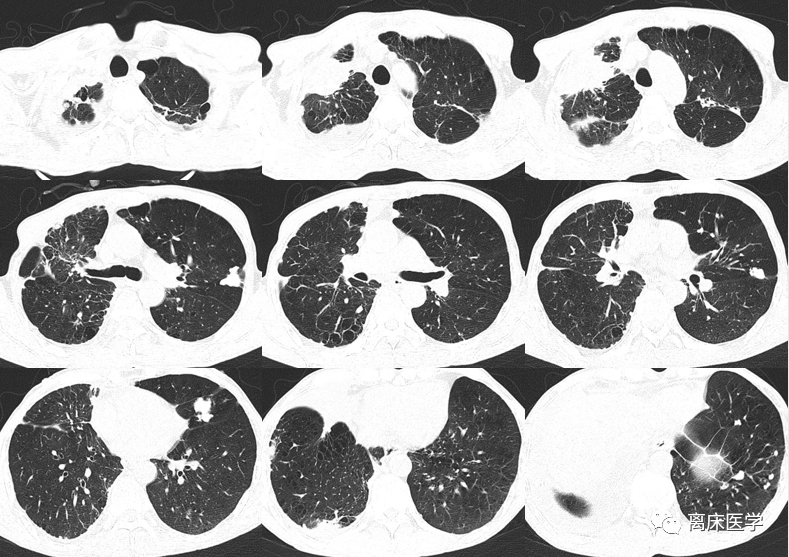

肺部阴影待查;2.胸腔积液.